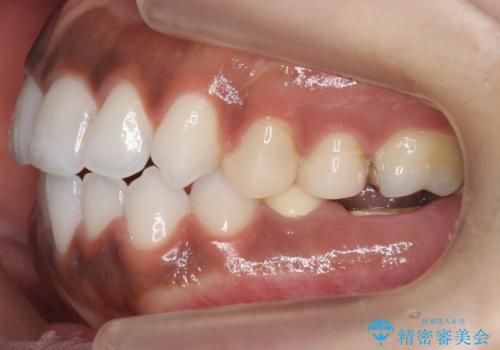

奥歯の高さがない 20代で入れ歯もインプラントも難しい ブリッジで歯を残す治療

虫歯を放置したため、左下奥歯の上下の歯の隙間が全くなく入れ歯もインプラントも難しい状態でした。

左下6番は残根状態だったため、やむなく抜歯を行い、⑤6⑦ブリッジとしました。

歯周外科手術を併用し、骨の高さを調整して歯の高さをしっかり出す手術(クラウンレングスニング)も行いました。